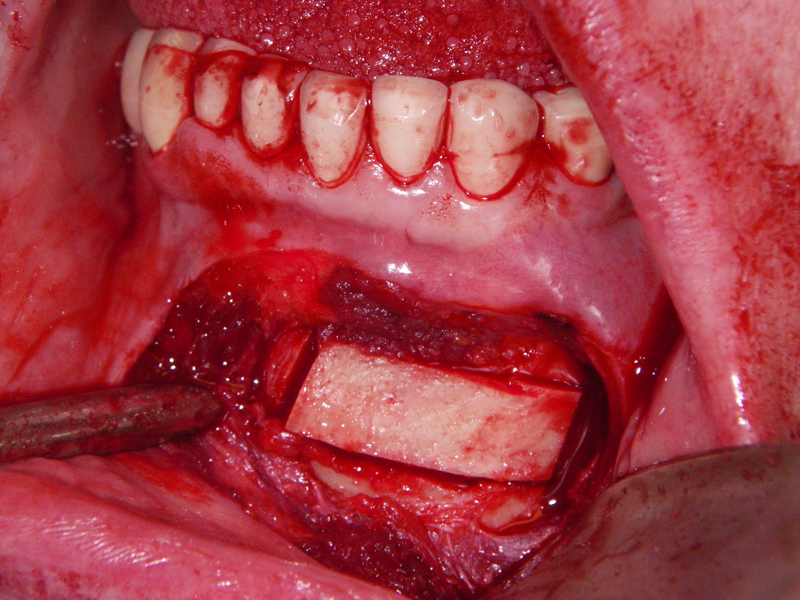

- Alveolar Ridge Augmentation

- Bone grafting – autogeneous, alogenic, xenogenic

- Blockgraft